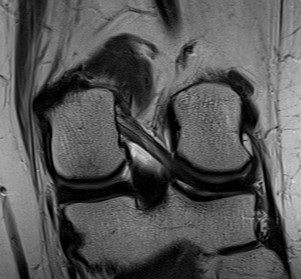

Posterior subluxation of tibia

Grade 3 PCL disruption - posterior tibia subluxed behind posterior aspect femoral condyles

MRI

PCL completely torn

PCL midsubstance tear with lengthening

PCL tibial avulsion

PCL femoral avulsion